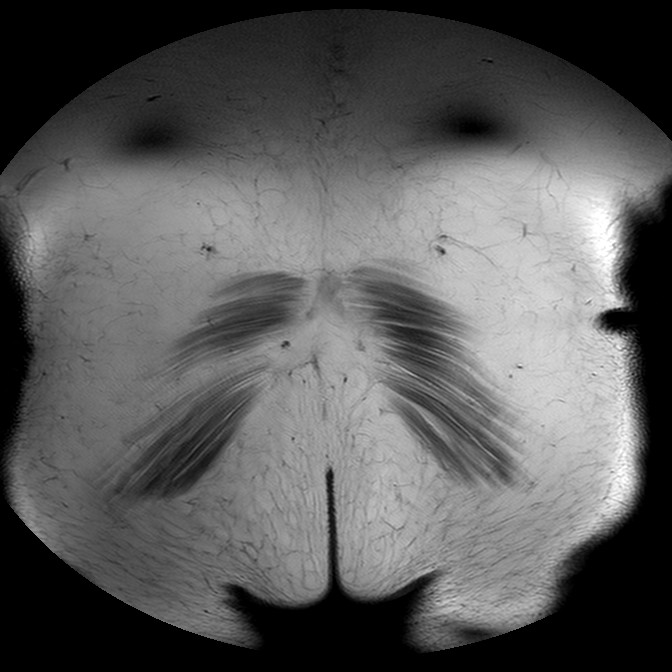

Esami: RMN BACINO

T1w TSE

Evidenti e simmetriche alterazioni osteofitosiche in regione coxo femorale con riduzione delle rime articolari. Degenerazione completa del cercine glenoideo. Non attuali segni di versamento articolare. Non segni di edema osseo che escludono attuale algodistrofia od osteonecrosi. Lieve e simmetrica riduzione del trofismo della muscolatura glutea.